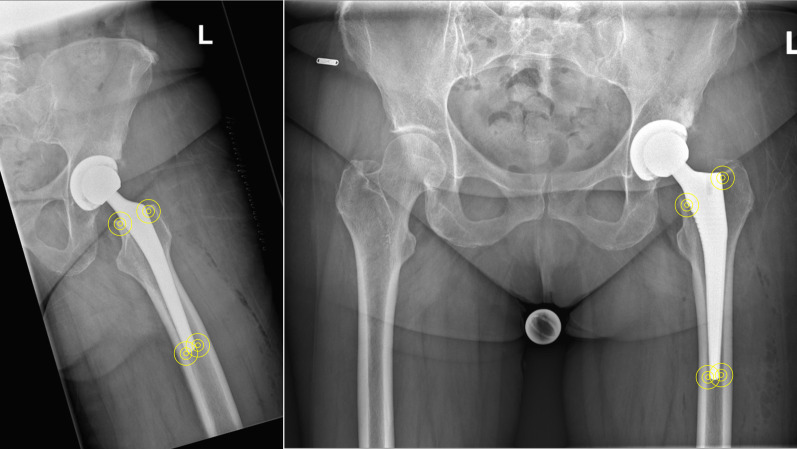

Methods: The present study was conducted following the STROBE guidelines. The records of patients who underwent THA between 2016 and 2023 were accessed. All patients who underwent two-staged bilateral THA were retrieved. The direct contact between the stem and the cortical bone was assessed at various points in the metaphysis and the distal portion of the stem (diaphysis) in both anteroposterior radiographs of the pelvis (medial and lateral bone contact) and a Lauenstein view of the hip (anterior and posterior bone contact). The following parameters were measured and compared to assess stem subsidence: distance from the proximal femur at the stem bone interface and the tip of the lesser trochanter (distance A); distance from the tip of the lesser trochanter and the tip of the femoral stem (distance B).

Results: In total, 250 patients were included, 45% (149 of 250 patients) were women and 61% (153 of 250 THAs) were implanted primarily on the right side. The mean age of patients at the time of the first THA was 64.3 ± 10.0 years and the mean body mass index (BMI) was 28.0 ± 4.9 kg/m2. The mean length of the follow-up was 14.1 ± 10.8 months. The overall stem subsidence following THA was 2.8 ± 0.7 mm (P < 0.006). A direct cortical bone-implant contact did not exert a statistically significant difference in subsidence of the THA stem at the metaphysis and diaphysis (P > 0.5). Stem subsidence following THA with a collarless cementless Corail stem was approximately 2.8 mm at 14 months.